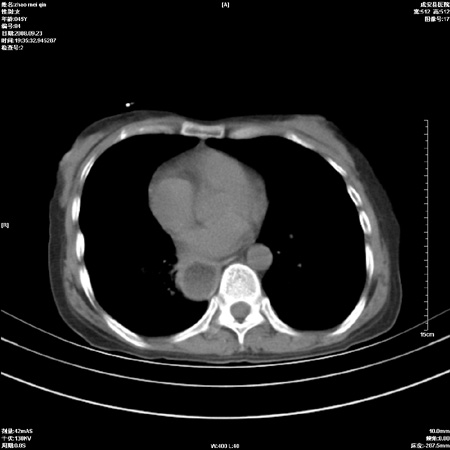

标题: CT15861:女 60 外伤后1小时 胸疼 [打印本页]

标题: CT15861:女 60 外伤后1小时 胸疼

外伤后1小时 胸疼 是外伤后引起的吗?

食道扩张明显下端逐渐变窄,倒像贲门失迟缓

考虑术后改变(胸腔胃),建议询问病史.

非外伤性改变,典型的贲门失迟缓症

食道扩张明显下端逐渐变窄,大量食物存留,象贲门失迟缓症。